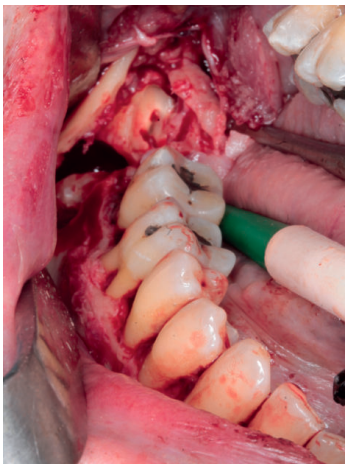

La cirugía se planteó bajo sedación y con el doble objetivo de la eliminación completa de la lesión con el cordal asociado y evitar un debilitamiento excesivo de la mandíbula. Para ello, se realizó un triple acceso a la lesión que nos permitiese por un lado despegar el quiste en toda su extensión mediante el uso de periostotomos y cucharillas de legrado, y por otro lado preservase una serie de “arbotantes” óseos que a su vez permitieran la posterior colocación de una mini placa desde la rama mandibular hasta el cuerpo, que actuase como refuerzo estructural (Figura 4).

A nivel local, se anestesiaron los nervios alveolar inferior y bucal mediante articaina 40mg/ml con 0.01 mg/ml de epinefrina (Ultracain® , España). Se realizó una incisión intrasulcular a espesor total con una descarga distal alta en la rama mandibular que se extendió hasta distal del canino inferior izquierdo sin necesidad de realizar una descarga en este punto. Se despegó el colgajo con la ayuda de un periostotomo para poder acceder a la superficie ósea. Con pieza de mano y fresa redonda de carburo de tugsteno se realizaron tres cavidades equidistantes: la primera a la altura del trígono retromolar (Figura 5), la segunda apical a los premolares inferiores derechos y la tercera mesio-apical al canino inferior derecho. Dichos accesos permitieron abordar y despegar toda la lesión en su extensión para posteriormente poder traccionar de ella a través de la cavidad media (Figuras 6 y 7). La cavidad posterior sirvió también para realizar la exodoncia del cordal (Figura 8). Tras la eliminación del quiste se llevó a cabo un legrado minucioso de la cavidad remanente y se limpió con agua oxigenada. A continuación, se colocó la mini placa con una extensión desde la rama mandibular hasta mesial de la cavidad media. Por último, se reposicionó el colgajo y se suturó de forma hermética mediante una sutura poliamida recubierta no reabsorbible de 4/0 Supramid (Aragó® ) (Figura 9). La muestra obtenida se conservó en formaldehido al 10% y se envió al anatomopatólogo, el cual confirmó el diagnóstico de quiste dentígero sin displasia celular (Figuras 10 y 11).